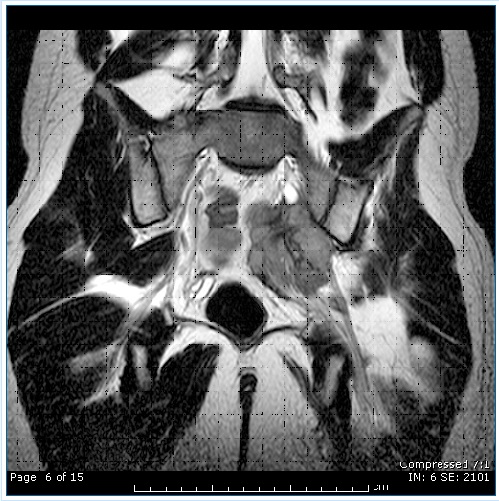

NEUROGRAFIA TECNICA IMAGENOLOGICA QUE PERMITE SEGUIR EL TRAJECTO COMPLETO DE LOS NERVIOS DE LA COLUMNA DESDE SU SALIDA EN LA MEDULA HASTABRAZOS Y PIERNAS

Tumor PNET comprimiendo el nervio ciatico

El sistema nervioso  periférico compuesto por plexos y nervios puede ser afectado por diversas patologías, las que pueden ser evaluadas desde el punto de vista imagenológico con esta herramienta diagnóstica y poner de manifiesto la presencia de inflamaciones compresiones y tumores entre otras causas

La neurografía ha demostrado ser capaz de poner de manifiesto la causa del origen del dolor en dolor lumbociático  y dolores radiculares en  diversas localizaciones, tanto cervicales como lumbares.